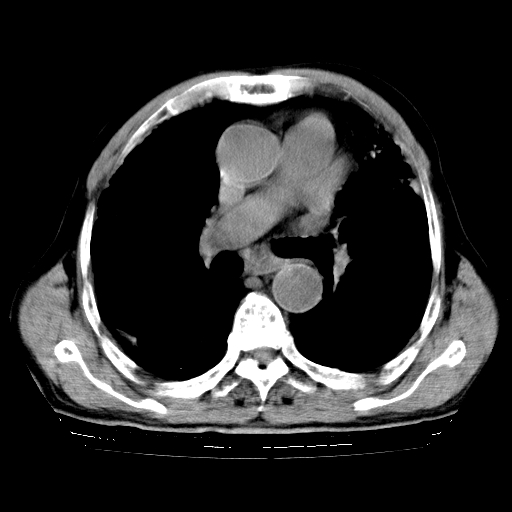

标题: CT25149:男,69岁,反复咳嗽、咳痰五年余,呼吸困难三天。 [打印本页]

男,69岁,反复咳嗽、咳痰五年余,呼吸困难三天。

慢支伴感染、肺气肿、肺心病

慢支伴感染、肺气肿、肺心病!支持!另:间质纤维化!

慢支伴感染、肺气肿、肺心病。双肺间质性改变(间质纤维化)。